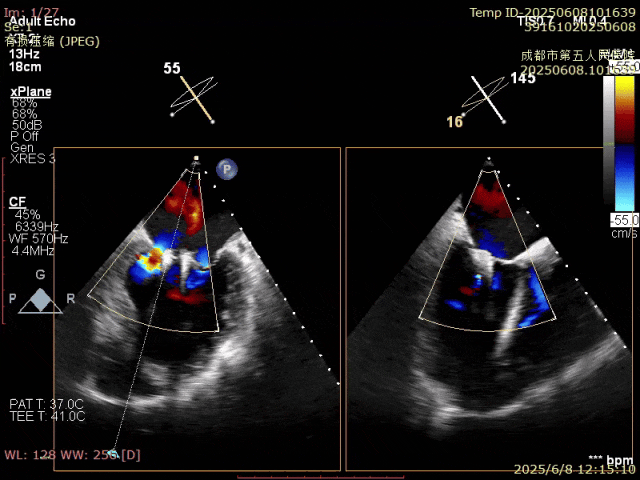

確認夾合位置及效果

即刻反流得到明顯改善